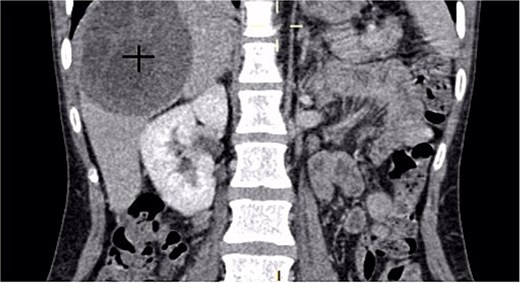

A 30-year-old woman, gravida 2 para 2, presented with a 10-day history of right upper quadrant (RUQ) abdominal pain. She had no significant medical or surgical history and denied systemic symptoms such as fever, weight loss, or fatigue. On examination, she was afebrile and hemodynamically stable, with a WHO performance status of 1. Abdominal palpation revealed localized tenderness in the RUQ. Laboratory investigations revealed mild leukocytosis (12 250/μL), Hb:10.8 g/dL, Plt:538000, TP:64%, Na:132 mmol/L, K:4.1 mmol/L, CRP:299 mg/L. Liver function tests showed GGT:36 U/L, PAL:46 U/L, ASAT:13 U/L, ALAT:6 U/L, total bilirubin:5 mg/L, direct bilirubin:3 mg/L. Urea and creatinine were 0.2 and 3.6, respectively. Contrast-enhanced CT revealed a large mass in the gallbladder bed, suspected to be a tubulo-papillary intracholecystic neoplasm (ICPN) (Figs 1 and 2), with an associated angiomatous liver lesion in segment III, hydatid cysts, and mild ascites. Exploratory laparotomy was performed, revealing a ruptured gallbladder tumor with extension into adjacent liver tissue and abdominal wall, and free biliary stones within the peritoneal cavity (Fig. 3).

A coronal CT scan of the abdomen showing a large, well-defined hypodense mass in the right hepatic lobe.